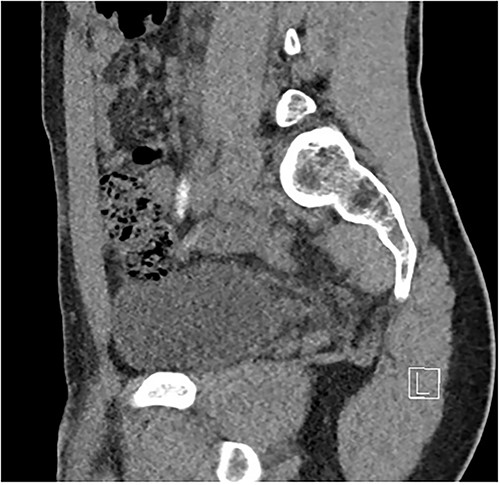

Two days following stent removal, the patient developed acute onset right lower quadrant and flank pain. A non-contrast CT of the renal tract was obtained to assess for procedure or stone-related complications. The scan demonstrated two distinct retained stones within the proximal right ureter, with associated moderate ureteronephrosis. Additionally, within the right lower quadrant of the abdomen, a radiopaque vermiform entity was demonstrated (Figs 1–3). This entity was not pathological, however, represented a normal appendix that had, consequent to contrast administration during a urological procedure, become filled with contrast secondary to vicarious contrast excretion.

Coronal imaging, demonstrating contrast-filled vermiform structure.